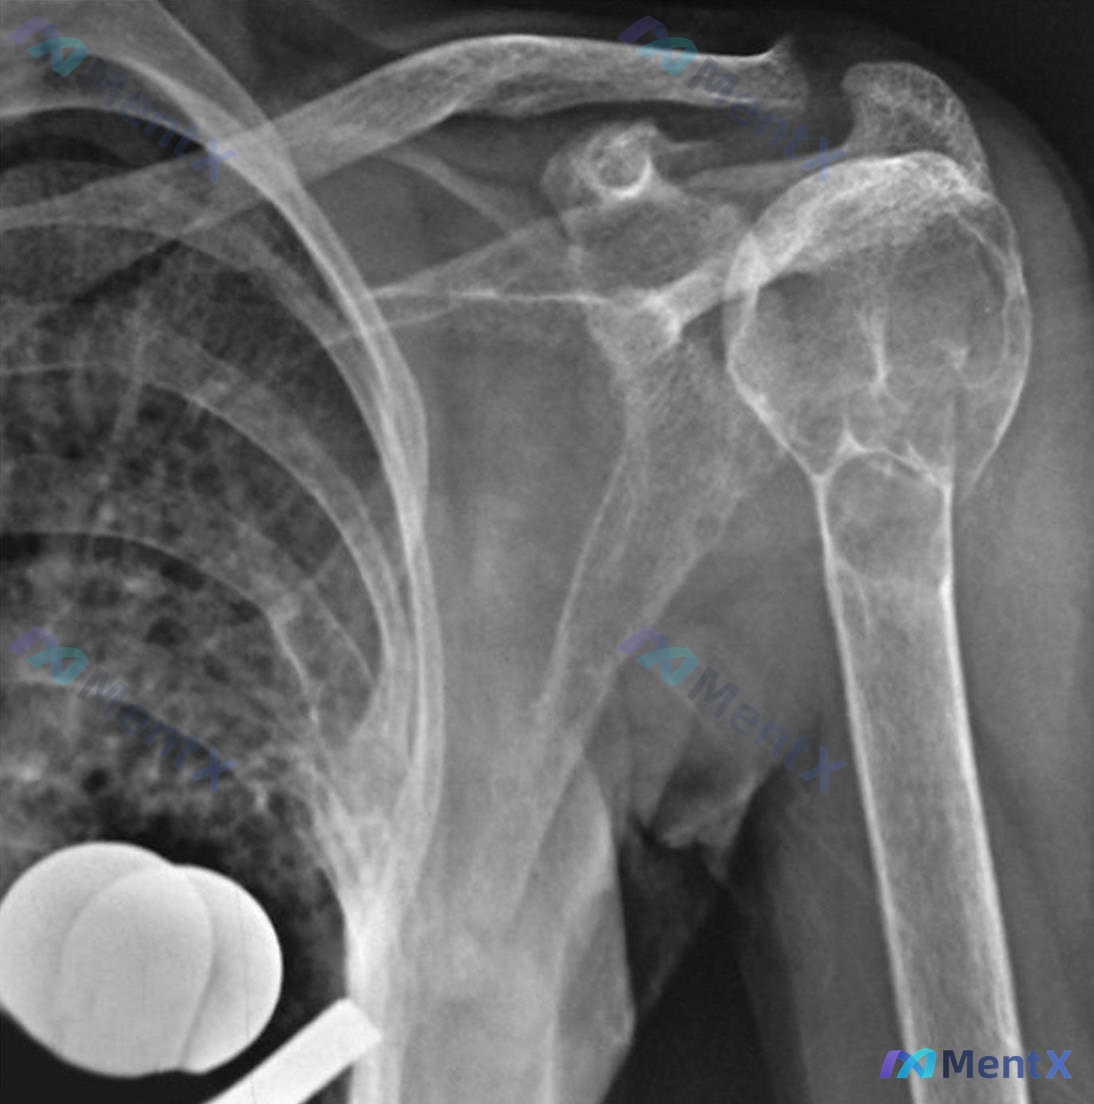

病例资料整理 患者信息:25 岁,女性。 主诉:5 个月前进门后左肩疼痛加剧。 既往史:2 年前曾因被地毯绊倒导致股骨骨折。 影像学检查: - 左肩 X 光:肱骨近端可见明显的溶骨性骨质破坏,病变区呈膨胀性生长,皮质变薄,骨小梁结构紊乱。 - 手腕 X 光:双侧手部及腕部骨密度普遍减低,多个掌骨及指...